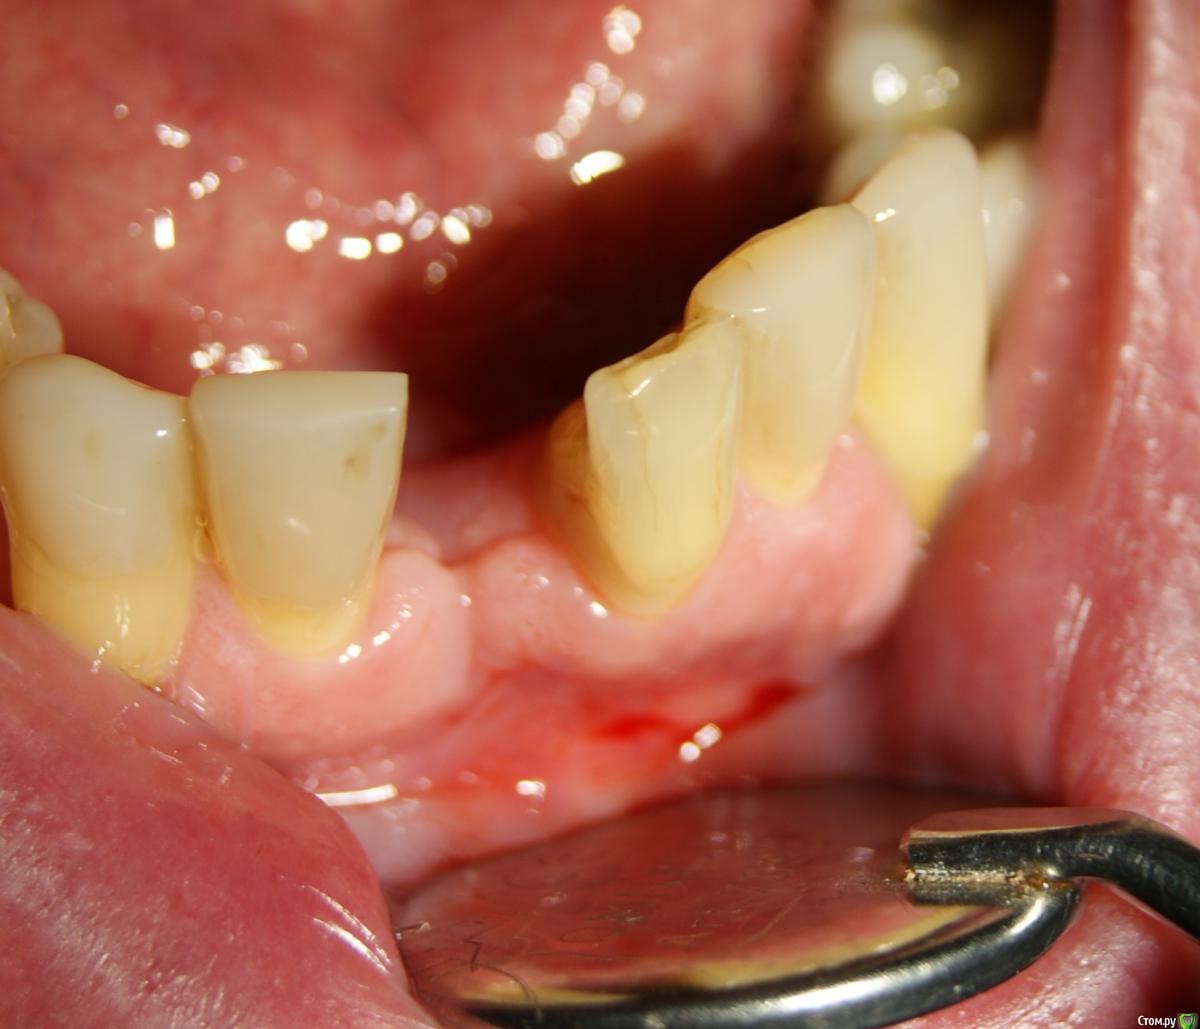

Jurai Опубликовано 25 декабря, 2016 Поделиться Опубликовано 25 декабря, 2016 *Предупреждение: фото на "мыльницу", не все этапы удались, но я работаю над этим) Вот пациент. Приятнейший, во всех отношениях, с негативным отношениям к мостовидным конструкциям. Полтора года лечил 41з по поводу периодонтита: толку не вышло. Удалил у широко известного многим стоматологам, особенно выпускам последних годов, доктора с ученой степенью. После удаления 4 месяца, по КТ область вполне достойно выглядит. Вот с чем пришел, обычное дело, все прилично: Раскрываю, а там между тонкими кортикалками мягко и упруго - резидуальная, фото нет. Открываю сильнее чем обычно, с расстройства не особо удачно. Кюретаж : Вид после, ушла вестибулярная кортикальная вместе с кистой: Сверлим 2,0, позиционердля рентген-контроля Имплантат ADIN UNP2,75Х11,5мм Ауто, джейсон коллагенфлис (что было под рукой) Швы. Контроль, перещелкивать не стали. В общем, понравился имплантат, для себя пометку кюретажить тщательнее, не надеяться, что организм все переварит. 1 9 Ссылка на комментарий

Jurai Опубликовано 26 декабря, 2016 Автор Поделиться Опубликовано 26 декабря, 2016 Сколько лет коротыш стоит?О, в области коротышки вообще трагедия про неудачную пластику. Изначально там было меньше 4мм до канала, делала пластику по Кюри с целью накрутить 34,35,36,37. Не удалось полноценно по многим причинам, от повторной пациент отказался. Порядка двух лет уже. Ссылка на комментарий